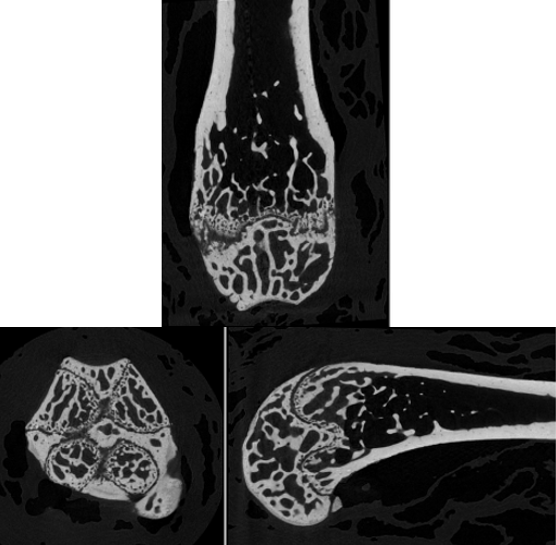

小鼠股骨的正交截面成像